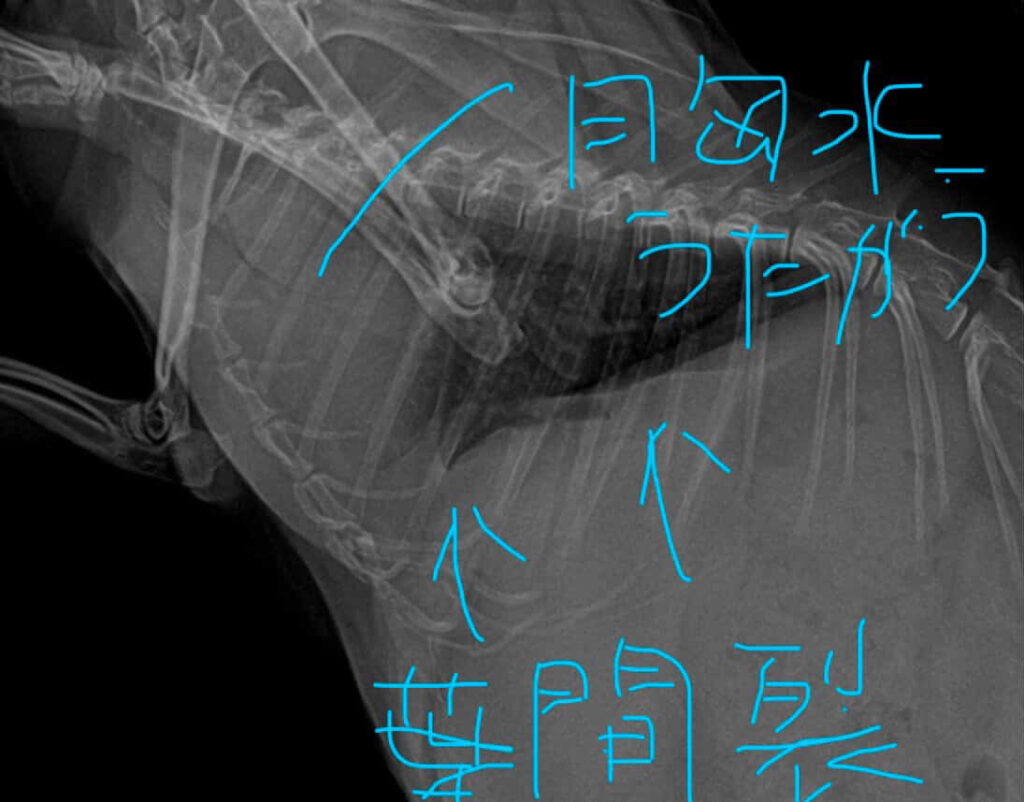

🩻 レントゲンが捉えた「胸水(きょうすい)」の疑い

さらに、レントゲン写真からは〝「胸水」の疑い〟があることが分かりました😣

◆ なぜ水が溜まっていると分かったのか?

レントゲンのコントラストに重なりがあり、白く霞んでいる部分があるのは、肺の周りに水が溜まり始めているサインだそうです😣